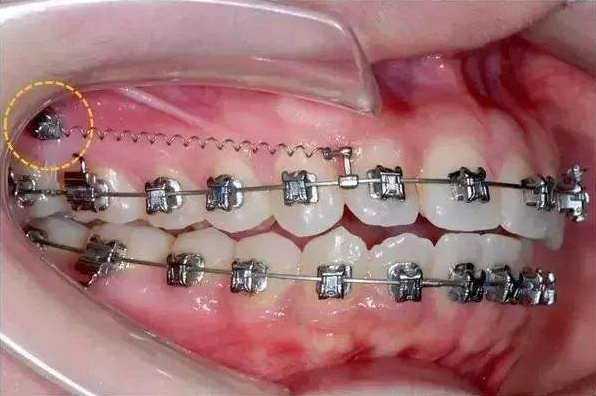

骨釘,顧名思義,是一種外形十分像釘子的種植釘,是放置在牙骨上方一個迷你的"釘子"。

它體積的小,好植入,近年來,逐漸成為正畸科常用的正畸輔助工具。

可不要看它體積小,卻在多種正畸方案中,成為醫(yī)生的得力助手,扮演著至關(guān)重要的角色

但是有了骨釘植入,就可以解決前者調(diào)節(jié)方案的煩惱,可以根據(jù)不同的調(diào)節(jié)方案,不同的調(diào)節(jié)需求,在口腔中相應(yīng)的位置植入骨釘形成口腔中的一個受力點(diǎn),同時利用正畸器,橡皮筋相互拉力的作用下,更好的幫助醫(yī)生更好的控制牙齒的移動,做到"該移動的牙移動,不該動的牙不動"從達(dá)到佳的調(diào)節(jié)果。